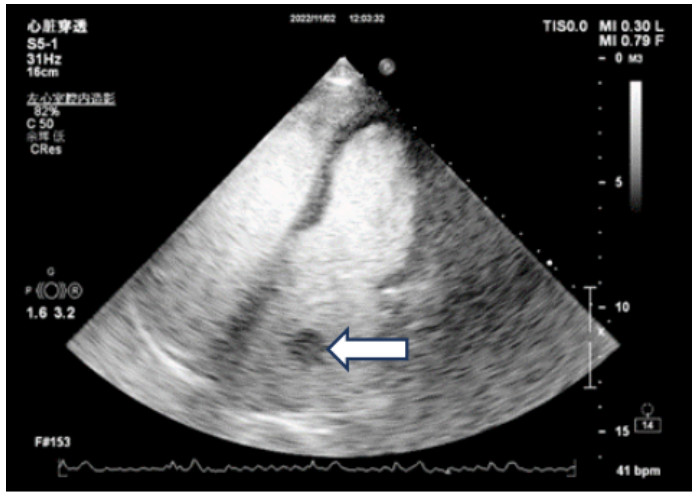

腹主动脉CTA成像示:腹主动脉近末端处-双侧髂总动脉-双髂外动脉、右髂内动脉、左髂内动脉起始部未见对比剂充盈,考虑腹主动脉急性闭塞(见图 4)。

| 注:A为冠状位,B为矢状位;腹主动脉远端未见对比剂充盈(箭头处) 图 4 患者主动脉CTA血管成像 |